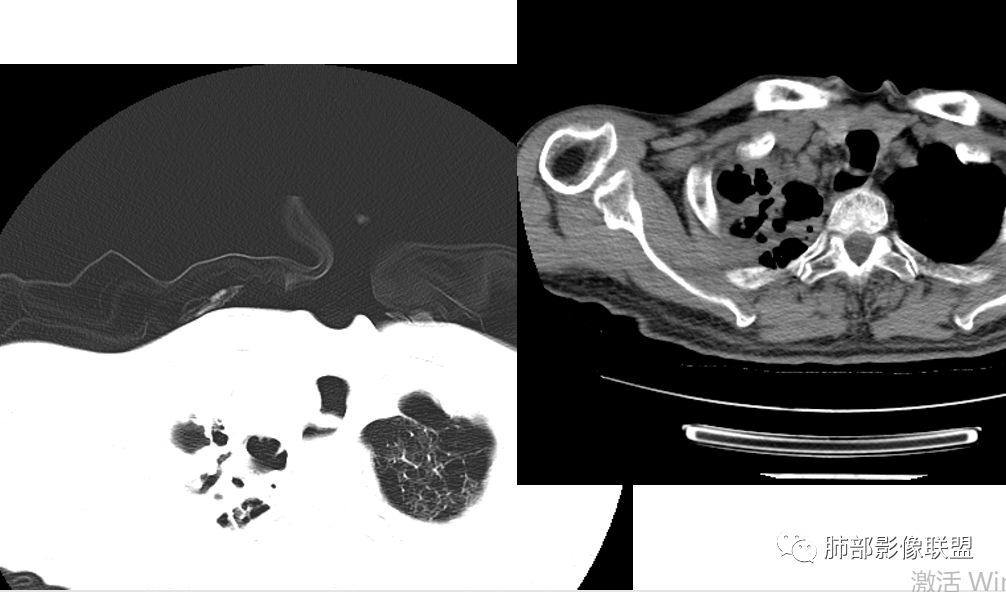

病例分析:双肺肺气肿,肺大泡,右肺上叶大片实变及空洞影,空洞壁光滑,部分有液平,病变自胸膜下向内,胸膜增厚,右肺下叶实变伴有空洞,右侧胸水,右肺门淋巴结肿大 ,抗炎治疗后变化不大,临床起病一周,有发热,血沉及降钙素高,肿瘤标志物稍高,结核干扰素阳性,首先考虑结核,鉴别细菌(空洞有液平)。

老年男性,起病急,感染指标高,肺部CT示肺气肿征象,双肺见肺大疱,感染病灶。予以碳青霉烯抗感染病灶出现明显进展,出现虫蚀样空洞、气液平。考虑患者细菌感染合并结核可能性大。但是结核进展可能太快了,需要排除真菌。

如果没有结果,分析是这样:这个人肺气肿基础,出现大片实变,那符合气肿性肺炎,头两次影像上还看不出结核来,但是白细胞不高,中性粒仅仅高一点的,然后血沉高,R干扰素高,抗感染不好。然后这个人有老年痴呆,初期可能会考虑这个人会不会只是一个细菌性肺炎呢,进展快。入院常规给与抗细菌没有问题。但是到11.08号影像出现一些端倪。一般气肿性肺炎虽然说可能好的不那么快,但是给与了亚胺培南这么高级的药反而进展,再加上血常规和一些实验室检查,好像普通细菌感染就有一点说不过去了。到第三次,出现空洞了,和肺气肿肺炎的气肿已经不一样了,气肿随着实变增加,里面应该会填实才对,但是出现空洞,这个说明不再是气肿里面的,而是真的空洞,而且还是那种肺尖的、光滑、有壁结节的空洞。

增强后里面密度整体低,比较支持坏死,一般炎症强化比较高,会有毛细血管新生,这个强化太低,提示坏死性炎症。这个还蛮符合干酪样坏死,实验室也支持。结核我感觉肯定有。